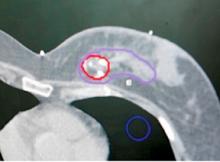

The trend in breast cancer treatment these days is all about precision, with the twin goals of controlling the cancer better and reducing side effects. Great advances have been made in radiation delivery methods that make it possible to more precisely target the tumor bed, plus a small margin around it where the cancer would be most likely to recur. By tightly focusing on these areas alone, radiation oncologists can minimize exposure to critical healthy tissue and structures such as the heart and lungs. Less damage to healthy tissue also means better cosmetic outcomes.